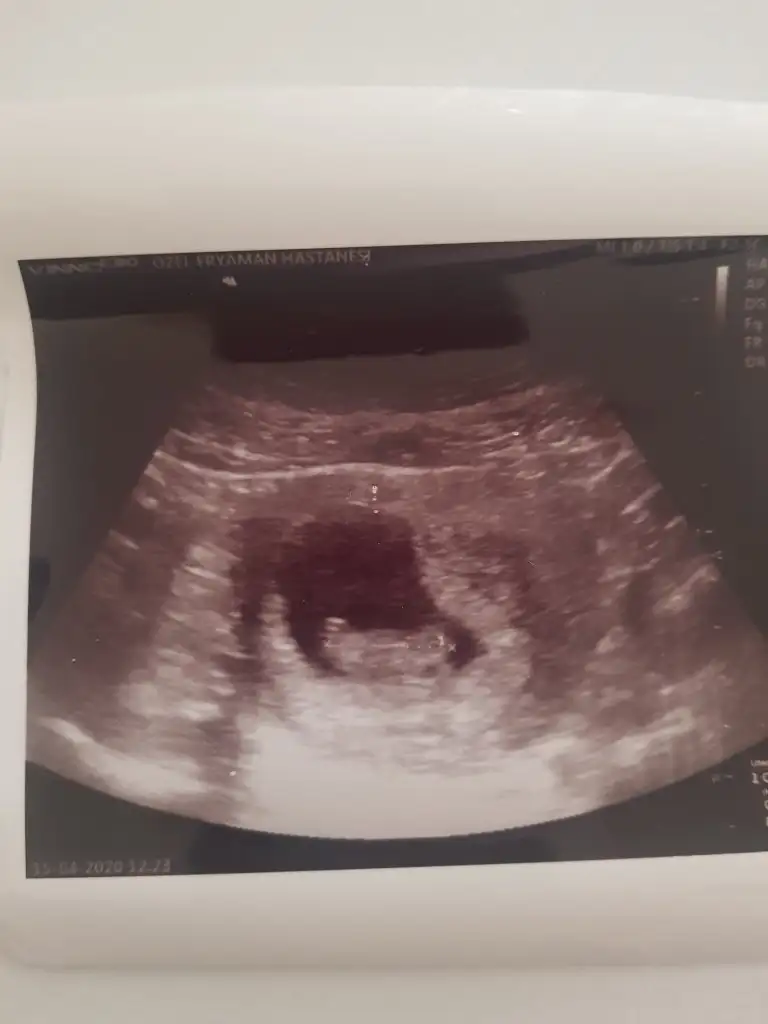

MaşallahKızlar buda benim bebişim bugün gittim yorumlayın bakalim kiz mi erkek mi

Merhaba cinsiyetten anlamıyorum ama crlniz kaç ve kaç haftalıksınız acabaKızlar buda benim bebişim bugün gittim yorumlayın bakalim kiz mi erkek mi

Maşallahburda kac hafta kaç günlük? Cinsiyet noktasında hiç bi fikrim yok

9+3 günlük kızlarMerhaba cinsiyetten anlamıyorum ama crlniz kaç ve kaç haftalıksınız acaba

Canım bu haftada nub teorisi var ama ben 7 haftalık haliyle falan yapabilirim9+3 günlük kızlarcrl 2.61 cm